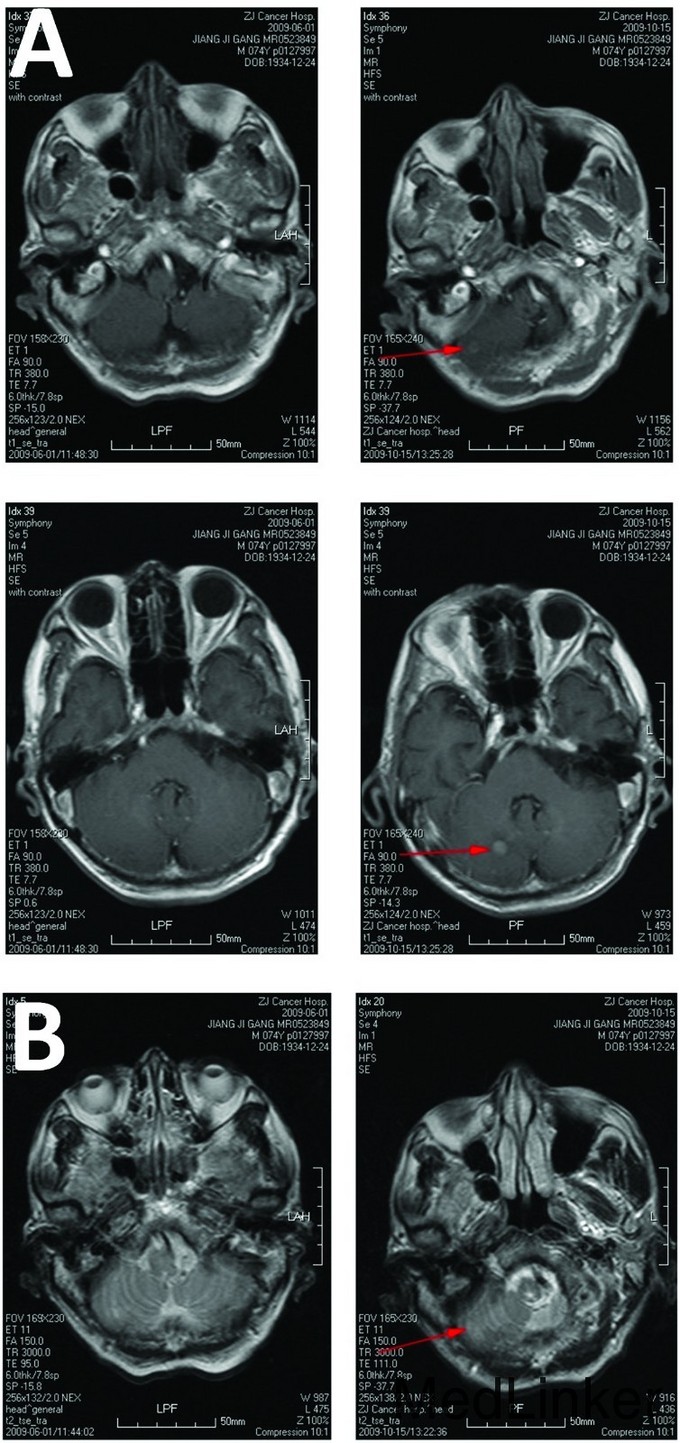

Cerebellar brainstem and spinal cord metastasis from esophageal cancer after radiotherapy is very rare. Here we report a case of a 74-year old male who was admitted to hospital with a poorly differentiated neuroendocrine carcinoma of the esophagus. After radiotherapy, multiple abnormal signals in the brainstem and spinal cord were found on magnetic resonance imaging (MRI). After treatment, clinical symptoms and abnormal MRI signals in the brainstem and spinal cord improved. This case revealed that brain metastasis from esophageal carcinoma may occur simultaneously with brainstem and spinal cord metastases.